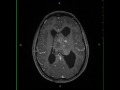

Atypical Neurocytoma

33-year-old female who presented with chronic headaches and papilledema. There is a lobular, predominately solid, T1-hypointense, T2/FLAIR-hyperintense mass arising in the body of the left lateral ventricle. Several prominent vessels are noted, and the lesion restricts diffusion. It contacts the lateral margin of the body of the left lateral ventricle as well as the septum pellucidum. The mass extends towards the foramen of Monro. There is mild post contrast enhancement, and there is increased blood volume. The differential includes subependymoma, subependymal giant cell astrocytoma, central neurocytoma, choroid plexus papilloma, meningioma and metastasis. This was an atypical neurocytoma. Central neurocytomas represent an intraventricular neuroepithelial tumor with neuronal differentiation . They usually occur in young adults presenting with headaches, papilledema, seizures, and altered mental status. The lesions are benign.